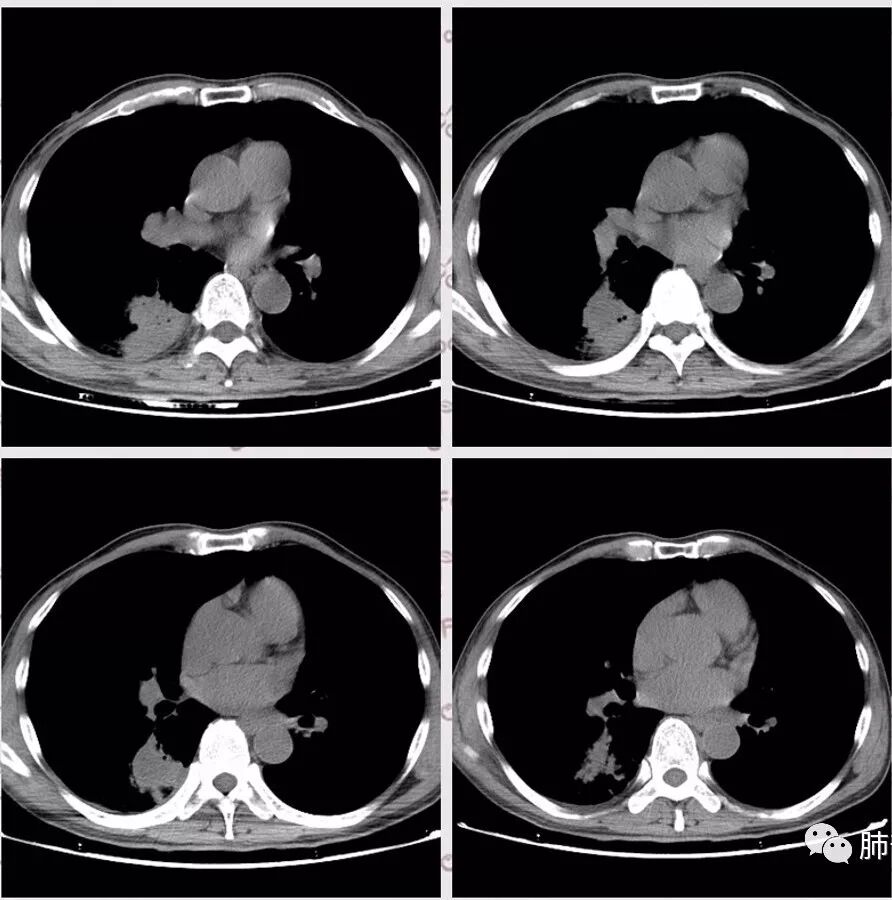

右肺下叶团块状密度增高影,边缘模糊,其内见液性低密度影,多发小气泡影及充气支气管征,考虑肺脓肿。颅内双侧顶叶长T2长T2病灶,周围水肿,DWI高信号,增强扫描囊壁环形强化,囊壁钙化,周围水肿,考虑脑脓肿。患者长期接触垃圾,什么菌都有,肺、脑脓肿,考虑肺克。再有肝脓肿就更支持了。

慢性病程,体质一般、接触垃圾,右下肺长轴与胸膜平行肿块,近肺门侧液化坏死伴多个小圆型空泡,肿块密度不均、不均匀强化,周围少量胸膜增厚,脑内多发空洞灶,考虑肺脑脓肿。鉴别肺腺癌脑转移。

胸部CT:右肺下叶背段实变,广基底,糊墙,长轴与胸膜平行,周围晕,支气管进入堵塞,纵隔窗可见低密度坏死,实变内小空洞?脑部不会看。

胸CT:右肺下叶背段实变影,内可见小空泡,病灶与胸膜呈宽基底,实变病灶周围存在毛玻璃影,纵隔窗可见病灶内存在低密度,增强可见病灶强化,并见病灶内低密度区。头MRI不会看。

右肺下叶背段实变,广基底,糊墙,长轴与平行胸膜,周围有晕,支气管进入堵塞,可见低密度坏死及小空泡。颅内多发环形强化灶,符合脑脓肿三层结构,结合临床,考虑:感染性病变,隐球菌?鉴别肺克。

肺内类三角形稍高密度病灶,边缘模糊,其内看见两个小气泡影。增强扫描欠规则厚壁中度强化,其内有轻度强化或未强化区。符合肺脓肿表现。

右肺下叶见不规则软组织影,边缘不清,内夹杂气体,背段支气管未见明显阻断,增强扫描下叶病灶内见类圆形低强化区,其边缘光滑,见低强化区壁,颅脑左侧枕叶及双侧顶叶见多发长T1长T2信号,T2高信号内见类圆形异常信号,壁呈低信号,DWI环形壁未弥散受限,内容物弥散受限,周围为水肿区,增强扫描呈多发环形强化,考虑血源型感染,颅内及右肺下叶脓肿形成

2.影像右肺下叶大片高密度影,整体边界模糊柔和,中央见圆形液化区及微小气泡影,内壁相当光整,环形强化,未见明确壁结节。双肺门及纵隔未见增大淋巴结。这样的病灶更符合细菌性肺脓肿,以肺炎克雷伯杆菌感染最为常见。